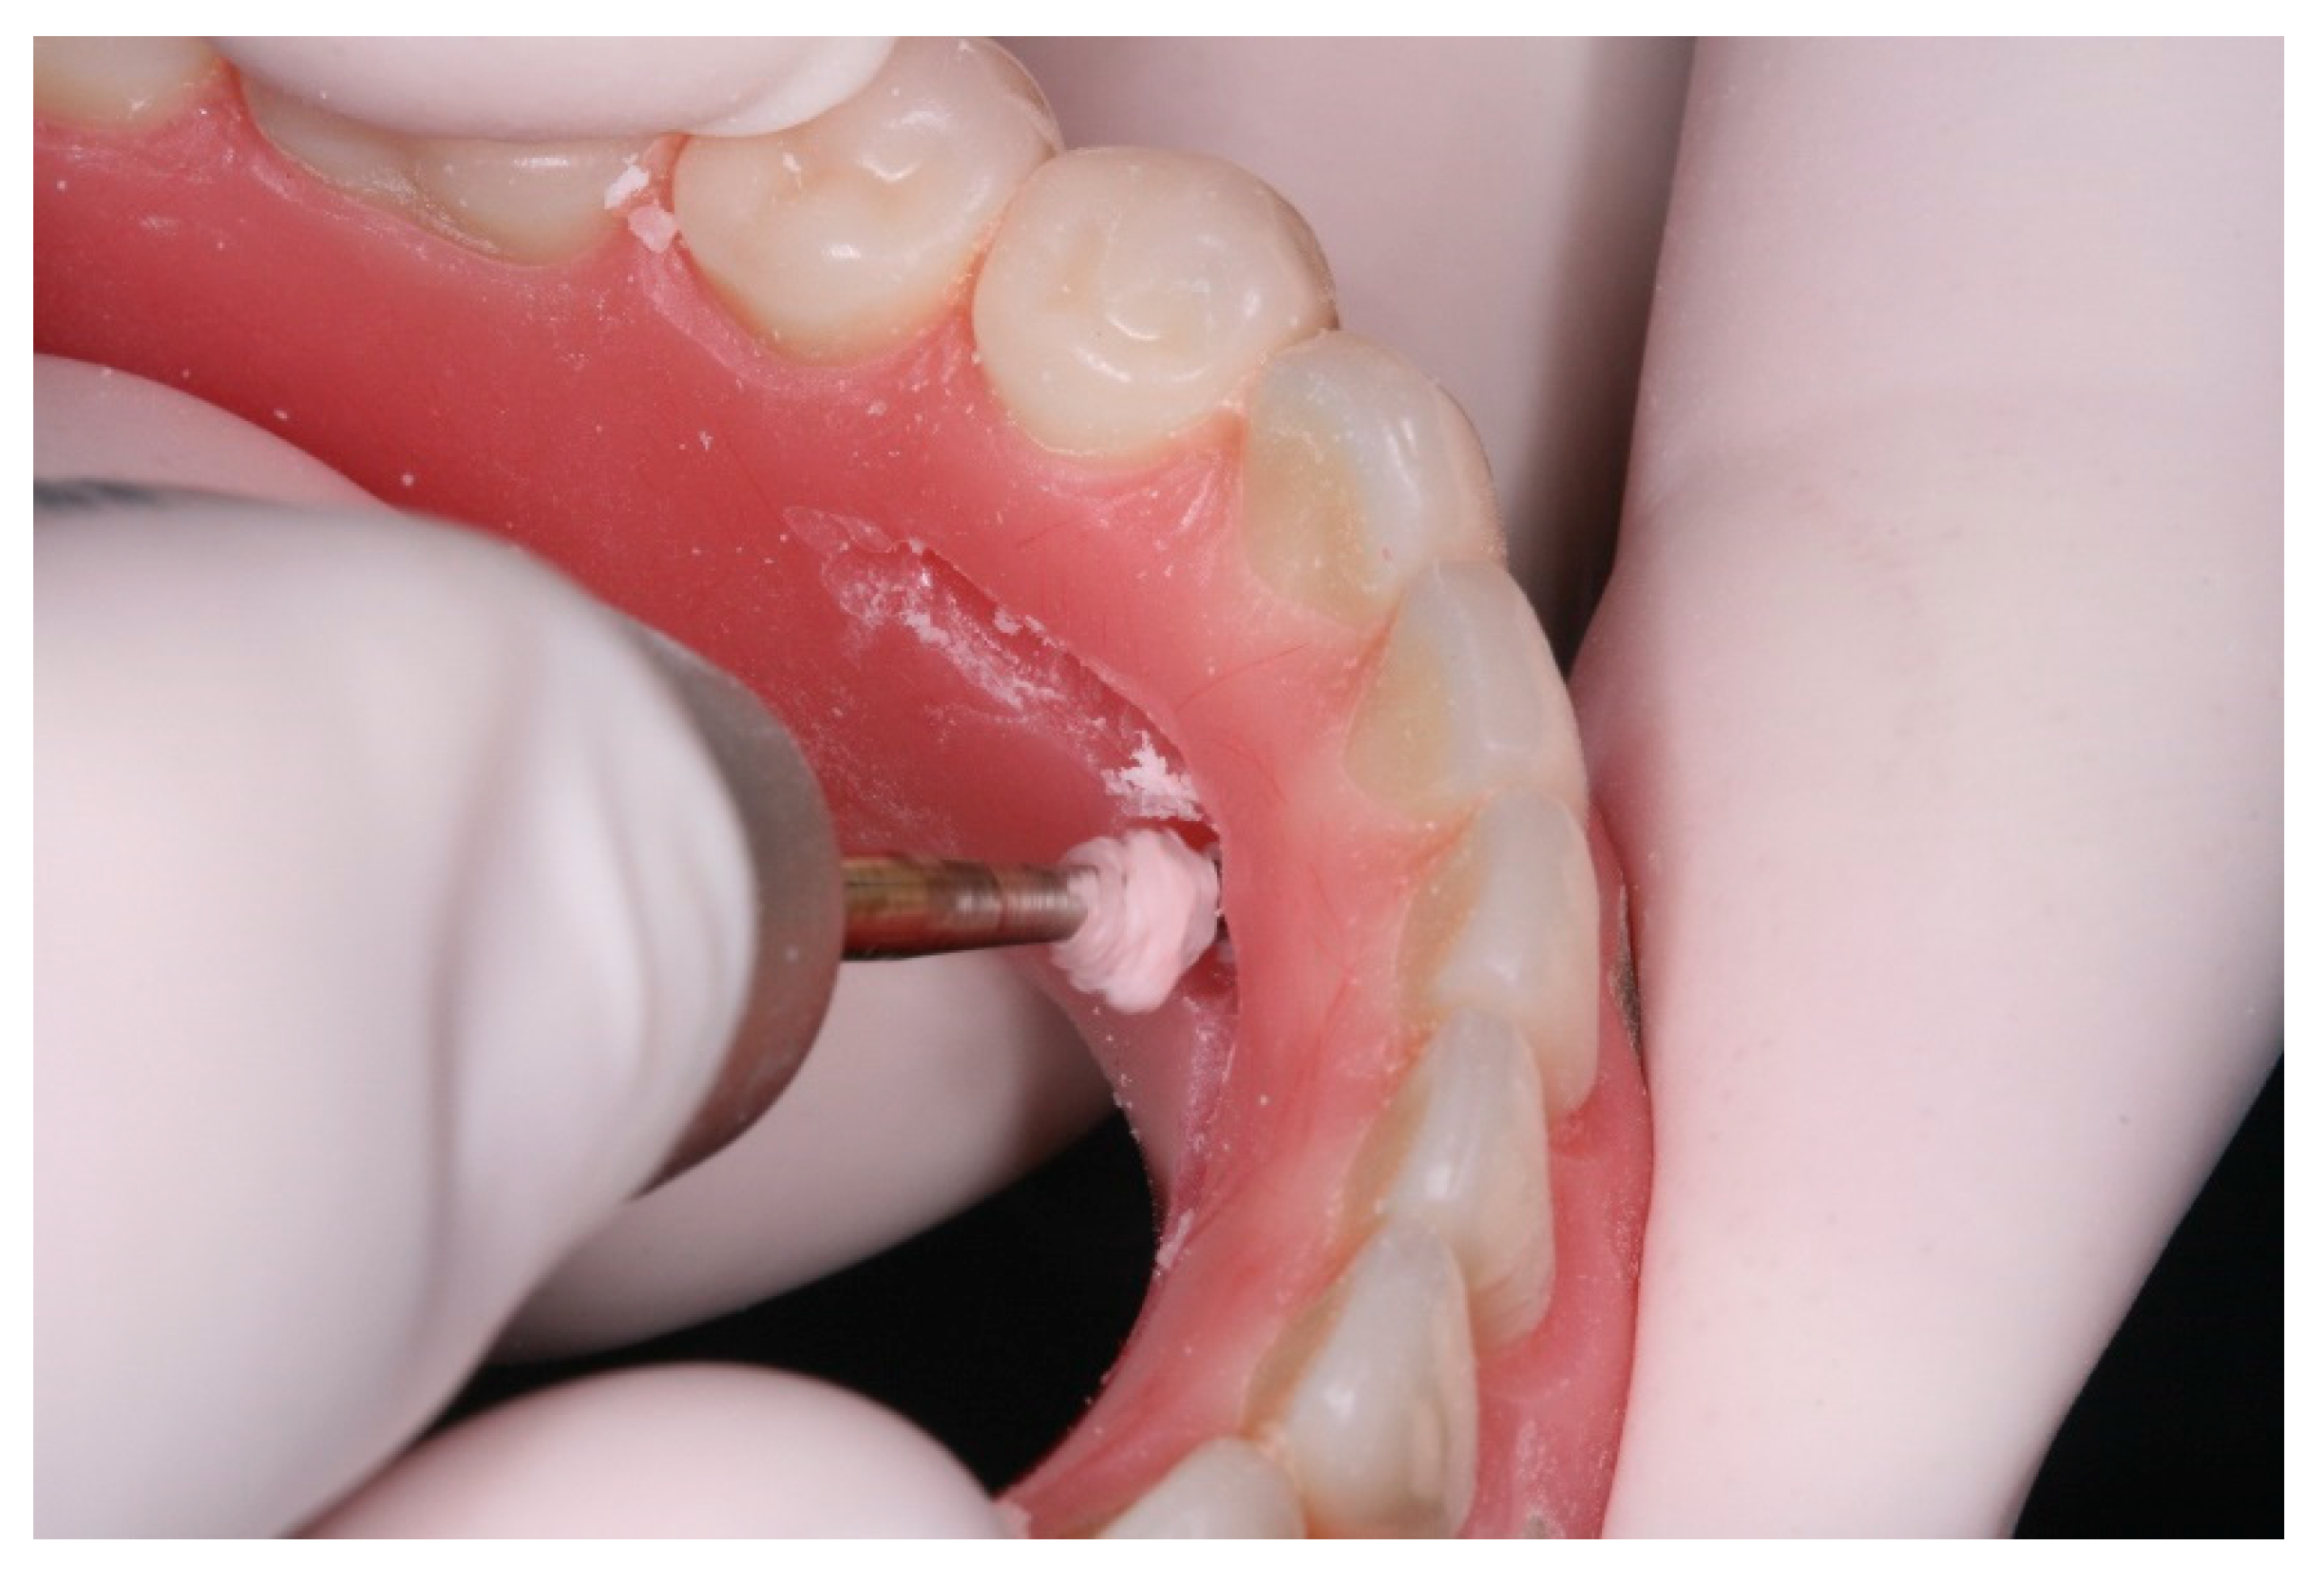

After a healing period of 3 months the patient returned to change que temporary fixed prothesis for a new one, more delicate and with a reinforced metallic bar for a better ferulization of the implants and better dissipation of the stress during function. After removal of the temporary prosthesis we could see the peri-implant mucosa was healthy (Figure 19), without bleeding on probe nor peri-implant sulcus with more than 3mm depth, even around the implants were there were lack of a satisfactory keratinized tissue band, showing us that the patient was being able to maintain the cleansing of the region below the prosthesis. A new fixed rehabilitation over the implants was produced (Figure 20, Figure 21 and Figure 22). 2 years after the surgery we could see on a control panoramic radiograph no signs of bone remodeling above the expected around the implants (Figure 23).

Figure 19. View of the peri-implants mucosa after 3 months of healing.